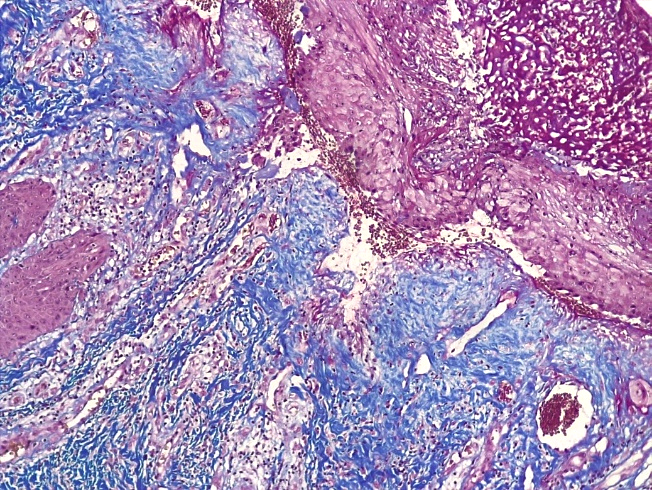

В случае длительного течения склероатрофического варианта течения СЛВ отмечалось резко выраженное сдавление мелких кровеносных сосудов в поверхностных слоях дермы за счет фиброзной соединительной ткани с гиалинозом стромы (рис. 20).

Рис. 20. Склероатрофический вариант течения СЛ. Под атрофичным многослойным плоским эпителием с признаками гиперкератоза отмечается фиброзная отечная ткань со сдавлением кровеносных сосудов и умеренновыраженной лимфо-гистиоцитарной инфильтрацией дермы (окраска по Пикро-Маллори, х100)

Fig. 20. Scleroatrophic variant of the course of SL. Under the atrophic multilayer squamous epithelium with signs of hyperkeratosis, fibrous edematous tissue with compression of blood vessels and moderate lymph-histiocytic infiltration of the dermis (Picro-Mallory coloration, x 100)